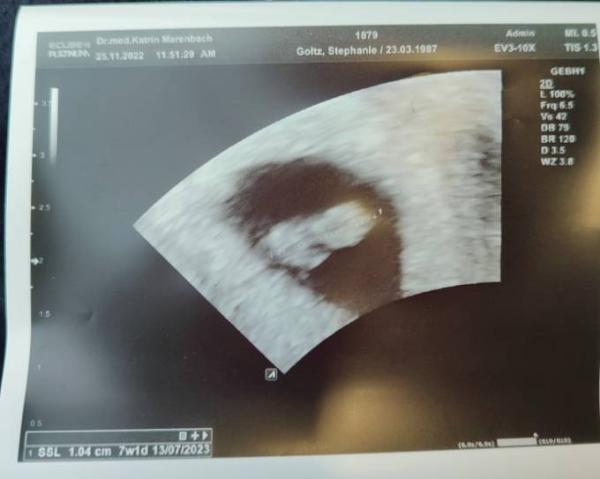

Nur komme ich gerade aus der Praxis und siehe da wieder schwanger . Ich könnte den Herzschlag sehen und hören und auf dem Ultraschall sieht alles gut aus. Ich muss in zwei Wochen wieder hin.

Nun sitze ich in der Bahn nach Hause und stelle fest das sie 7+1 festgestellt hat. Ich bin jetzt ziemlich verwirrt da die Absaugung ja erst 7 Wochen und 4 Tage her ist. Wie kann das sein? Leider ist Freitag und die Praxis hat nun schon zu. Hat jemand ähnliche Erfahrungen?